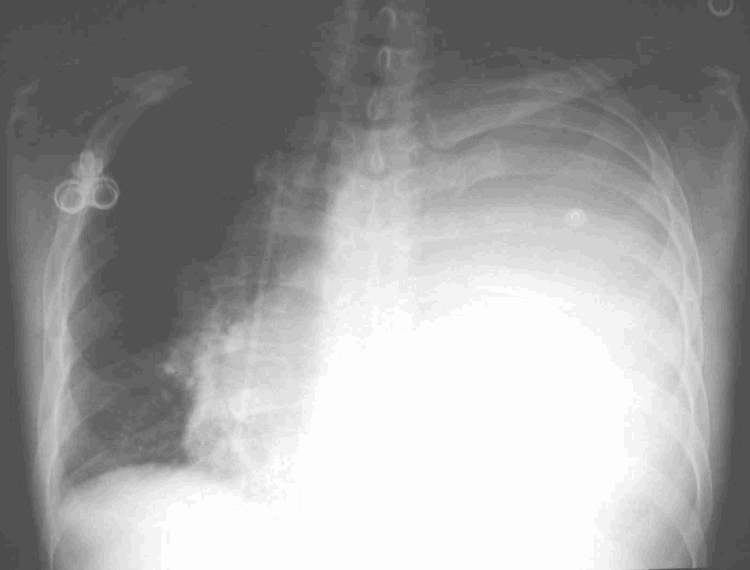

Pulmonary edema is usually treated with water pills. Thoracentesis is a procedure to remove fluid from the space between the lungs and the chest wall called the pleural space. Fluid can be removed with a variety of tubes, but frequently in order to keep it from coming back the lining of the chest cavity needs to be removed surgically with a procedure called a.

Fluid in lungs ( pulmonary edema) can be due to many causes: It is done with a needle (and some. How to get rid of fluid in lungs 1, some of the fluid.